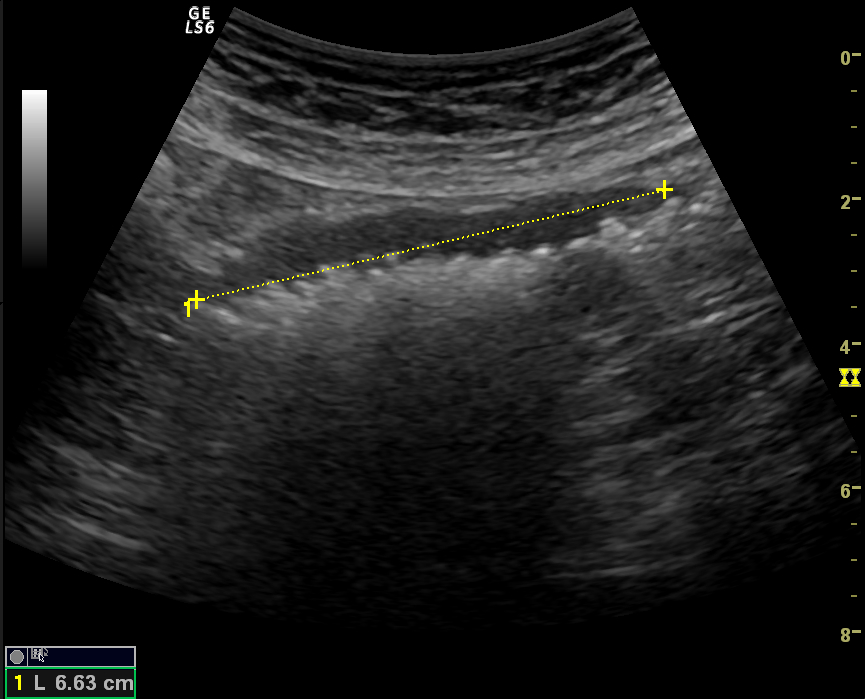

Acute abdominal pain is one of the most common conditions encountered in the emergency department. The differential diagnosis of acute abdominal pain is extensive and identifying the underlying etiology can be challenging. We report a case of acute transient ischemic jejunitis due to symptomatic isolated superior mesenteric artery dissection in a patient with no cardiovascular risk factors or autoimmune diseases. Symptomatic isolated superior mesenteric artery dissection is a rare cause of acute abdominal pain usually treated in the surgical department. The patient had criteria for conservative treatment and rapidly recovered. We highlight a rare condition which should be taken into account for the differential diagnosis of acute abdominal pain.